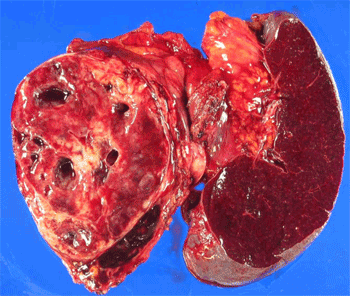

또한 함께 시행한 세포진단 검사에서도 "papillary fragment with fibrovascular core lined by small bland uniform cells"를 보였다 (Fig. 4). 특수 염색 검사에서도 synaptophysin, (weak, +); β-catenin, (nuclear, +); E-cadherin, ( - ); chromogranin, ( - ) 소견을 보여 SPT를 진단 할 수 있었다. 세포진 검사의 정확도는 약 75%이며, 다른 췌장의 신경내분비 종양과의 감별진단을 위해 vimentin, CD10, 그리고 β-catenin 등 특수 염색이 필요하다.

Figure 4. Many clusters of bland round cells with papillary configuration

이상의 검사 결과를 종합하여 SPT 의심 소견이고 타장기 전이가 없었으므로 수술적 절제(distal pancreatectomy with splenectomy)를 시행하였다 (Fig. 5). 최종 병리결과에서 SPT로 확진되었다 (Fig. 6).

Figure 5. Cut surface of the enbloc resected specimen; distal pancreatectomy with splenectomy